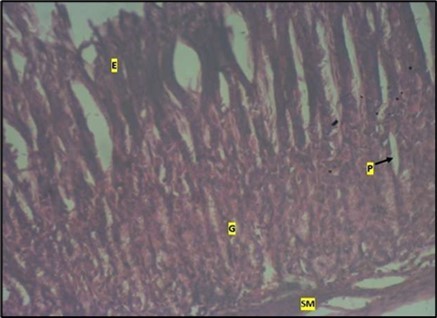

Histological examination of the stomach in control animals showed normal appearance of epithelial cells lining the mucosa and normal smooth muscles in the submucosa (Figure 8). However, administration of Abelmoschus esculentus at low dose showed deep epithelial gastric area with marked depletion of pits and goblet cells (circled area) and normal smooth muscles in the submucosa (Figure 9) and the high dose group showed dysplasia of gastric pits with goblet cells in the mucosa and the smooth muscles in the submucosa were mildly eroded (Figure 10).

Figure 8.control plate showing gastric pits with goblets cells (g). Smooth muscle layer (SM) and surface epithelium (e) appears normal. (H&E).

control plate showing gastric pits with goblets cells (g). Smooth muscle layer (SM) and surface epithelium (e) appears normal. (H&E).